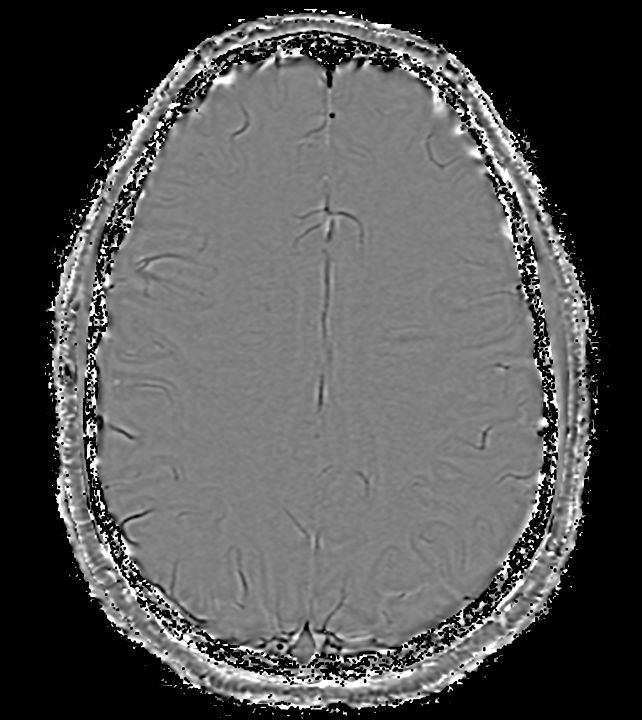

Axial SWIp (Modulus)

-